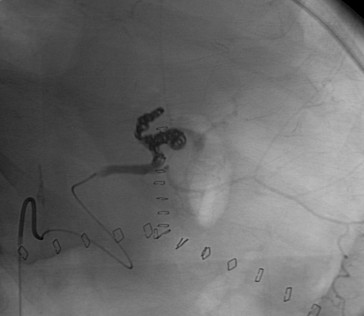

中年女性,间断左上腹部疼痛3个月,近期加重。CT显示10厘米的脾动脉瘤,近期动脉瘤内出血(瘤内血栓后再有血流入)。

trapping 前后门技术+packing

腹腔造影证实为一个巨大的动脉瘤,脾动脉既是近端供血,也是流出道。导管成功进入流出道。

腹腔血管造影的病人采取不同的投影,以更好的解剖可视化。血流入口(红色箭头)和流出口(黄色箭头)均暴露于脾动脉。在6Fr MachI作为引导导管的支持下,用5Fr 导管进入流出道,微导管经5F导管进一步进入流出道。

流入道 |

巨大脾动脉瘤是罕见的,并且由于其巨大的体积而难以栓塞。适用前后门栓塞的原则,但在如此大的动脉瘤中,后门插管是困难的。良好的支撑导管是关键。巨大的动脉瘤囊本身也被证明很难完全栓塞。可能需要不同栓塞剂的组合——在这种情况下是弹簧栓子/NBCA/凝血酶。以确保足够的流量进入这些巨大的动脉瘤。